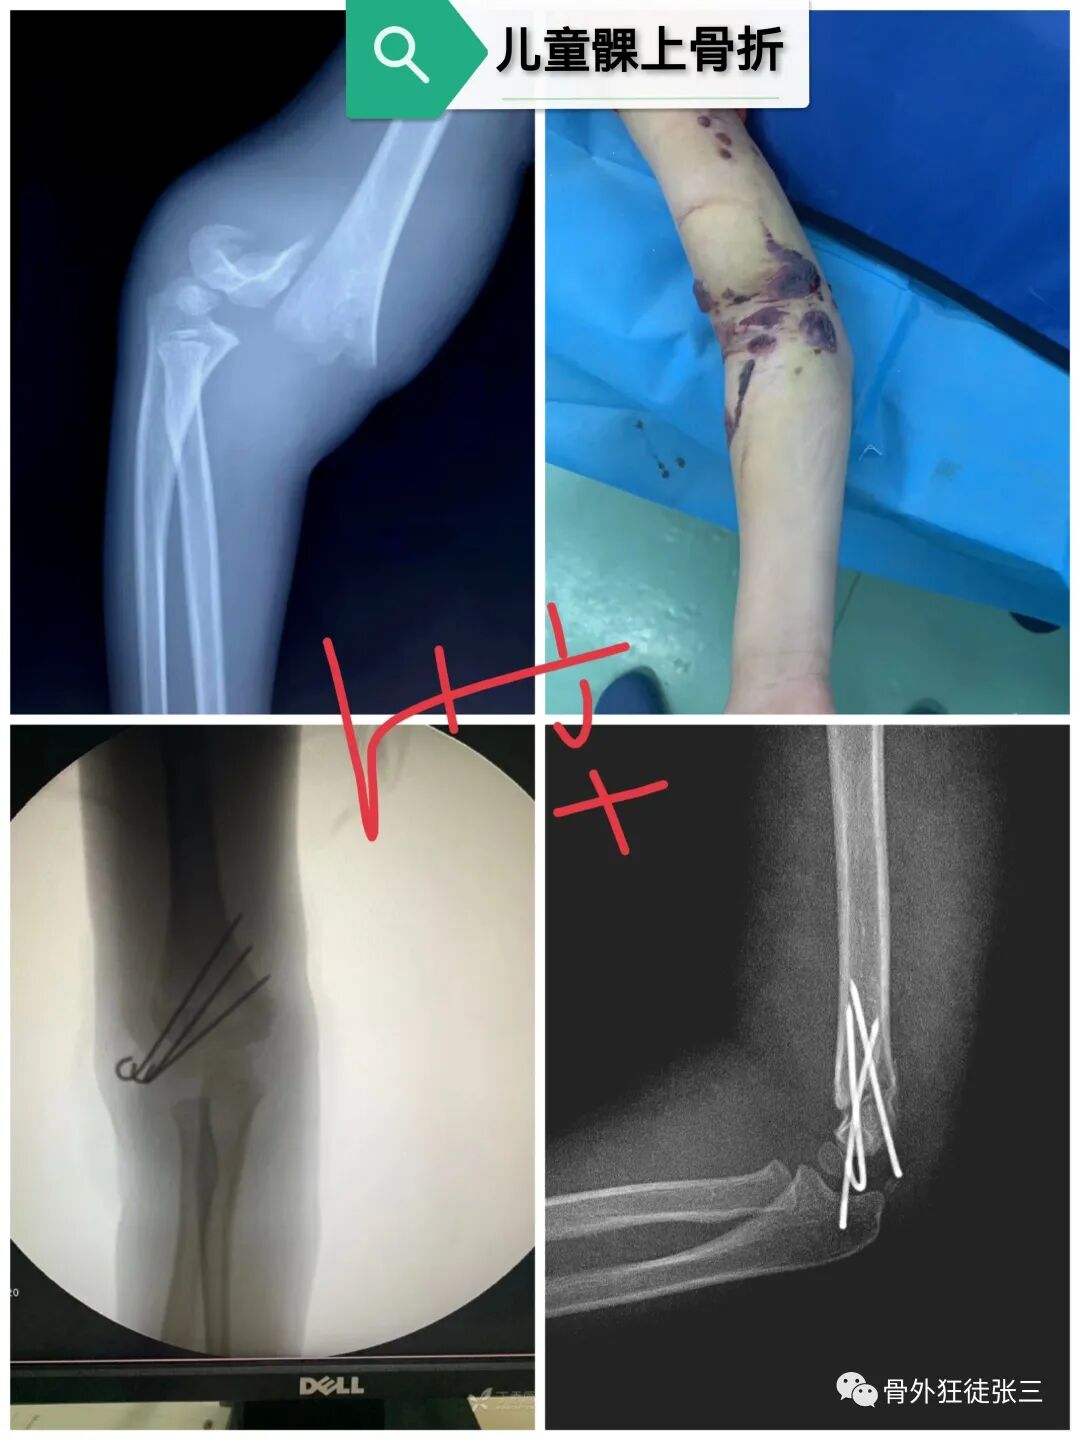

病例16,儿童髁上骨折零切开

病例17,低位髁上骨折零切开

病例31,儿童髁上骨折零切开,闭合复位克氏针

病例32,第345掌骨开放性骨折,克氏针髓内+克氏针支架